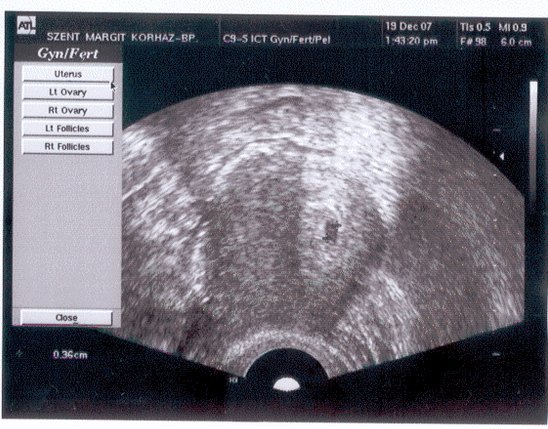

No, akkor íme Agisol uh-ja. :)

A legalsó sorban ott van, hogy + 0,36 ez az én uh-mon azt jelentette, hogy a két + jel között van a babó, és a két jel közti távolság a 0,36 cm, tehát ekkorának látja a gép.